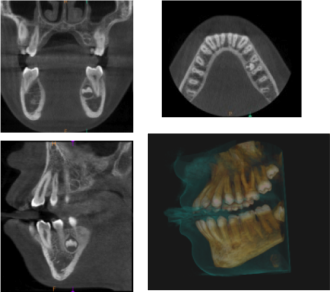

CÔNE BEAM